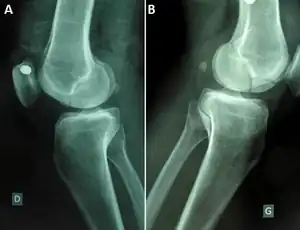

| Stieda fracture | Alfred Stieda | avulsion fracture of the medial femoral condyle at the origin of the medial collateral ligament | Stieda's fracture Archived 2022-05-17 at the Wayback Machine at TheFreeDictionary.com | ||

| Segond fracture | Paul Segond | lateral tibial plateau avulsion fracture with anterior cruciate ligament tear | Segond fracture at Who Named It? | ![]() | |